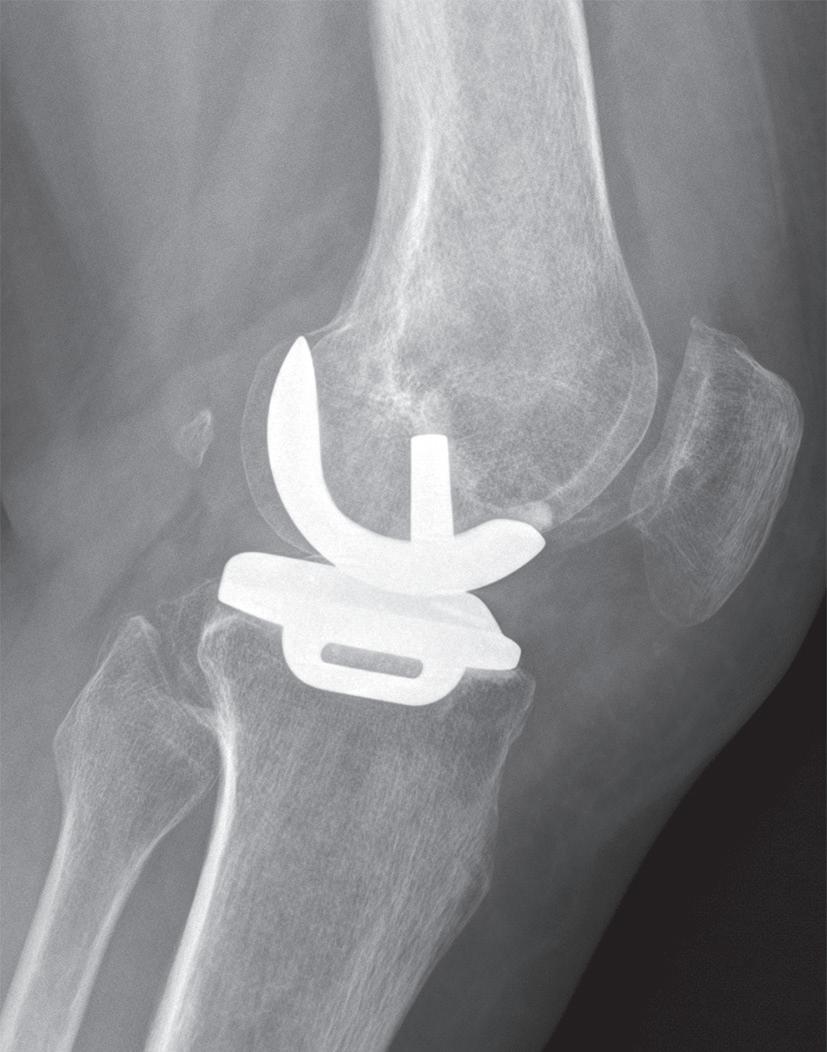

Při poškození pouze mediálního kompartmentu kloubu bez větší osové odchylky je metodou volby hemiartroplastika za použití speciálního implantátu (obr. 19.10, obr. 19.11). Tento výkon pacienta poměrně málo zatěžuje a rehabilitace je jednodušší než u osteotomie nebo totální endoprotézy. Podmínkou je nepoškozený přední zkřížený vaz a dobrý stav patelofemorálního kloubu. U mladších nemocných si obvykle po přibližně 15 až 20 letech vyžádá výměnu za totální endoprotézu.

Obr. 19.11: Hemiartroplastika – předoperační (a, b) a pooperační rentgenový snímek (c, d)